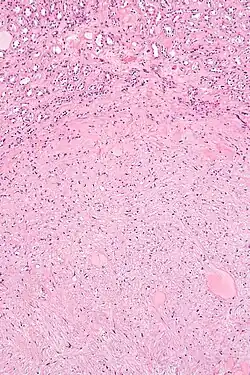

| Micrograph of a renal medullary fibroma (bottom of image). Renal tubules are seen at the top of the image. H&E stain. | |

Renal medullary fibroma is a benign kidney tumour. It is commonly an incidental finding.[1]

They consist of bland spindle-shaped or stellate-shaped cells in a loose stroma. Renal tubules may be entrapped.